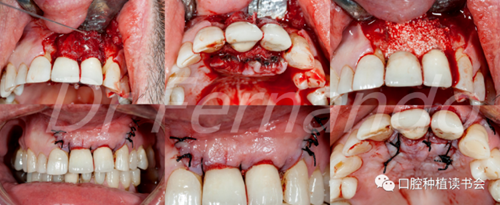

圖4 前牙美學(xué)區(qū)種植體周圍炎采用手術(shù)&骨再生治療

盡管手術(shù)治療似乎能改善結(jié)果;但只有將手術(shù)治療和骨再生相結(jié)合才能獲得更高的成功率。Schwarz等人發(fā)現(xiàn)這種再生手術(shù)治療有2年以上的滿意效果,能使種植體周圍的骨吸收停止,探診出血率由80%降至34%(圖5 )。

圖5通過手術(shù)治療,種植體周圍獲得骨再生,術(shù)后2年效果穩(wěn)定(圖2、圖4相同病例)